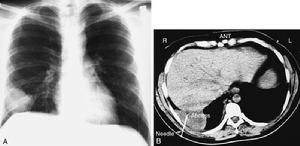

1.胸部X線檢查是肺膿腫的主要診斷方法。由於膿腫有向不同葉蔓延的特點,可波及多葉甚至全肺。但如一開始就發生在上述以外的部位,要懷疑有特殊的病因,如腫瘤堵塞性膿腫或肺囊腫感染等。肺膿腫在各不同階段病理改變很大,X線也有很大不同。急性期(在1周內)為大片緻密模糊陰影,按葉段分布呈楔形,尖向肺門,外側緊貼胸廓,縱隔或葉間胸膜面;在治療下,陰影改變較快。當膿腫與支氣管相通時,即出現空腔,由於引流支氣管多不通暢,加上體位因素,膿液不能完全排出,片上常見液平面。因壁厚,加上周圍仍有炎症,腔外有厚層,雲霧狀炎症浸潤影,慢性的周圍還有纖維化。空腔大小、形態不一,可呈圓形、橢圓形或不規則形,不少是多房的。經治療後如好轉,則空腔漸縮小、消失,留下纖維條索狀陰影及胸膜肥厚影。

2.CT檢查斷層(包括CT)可更好了解病變範圍、部位、空腔情況。少數膿腫內膿液未排出,表現為圓形塊影,但在可見內有小空洞,真正呈實塊的不多,易誤為腫瘤。纖維化明顯的肺體積縮小,支氣管完全閉塞可有肺不張。可

見葉間胸膜增厚。膿腫破向胸腔形成膿胸或膿氣胸,片上有相應改變。